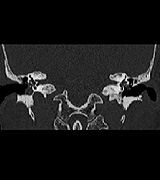

CT画像

• ct01

• ct02

• ct03

• ct04